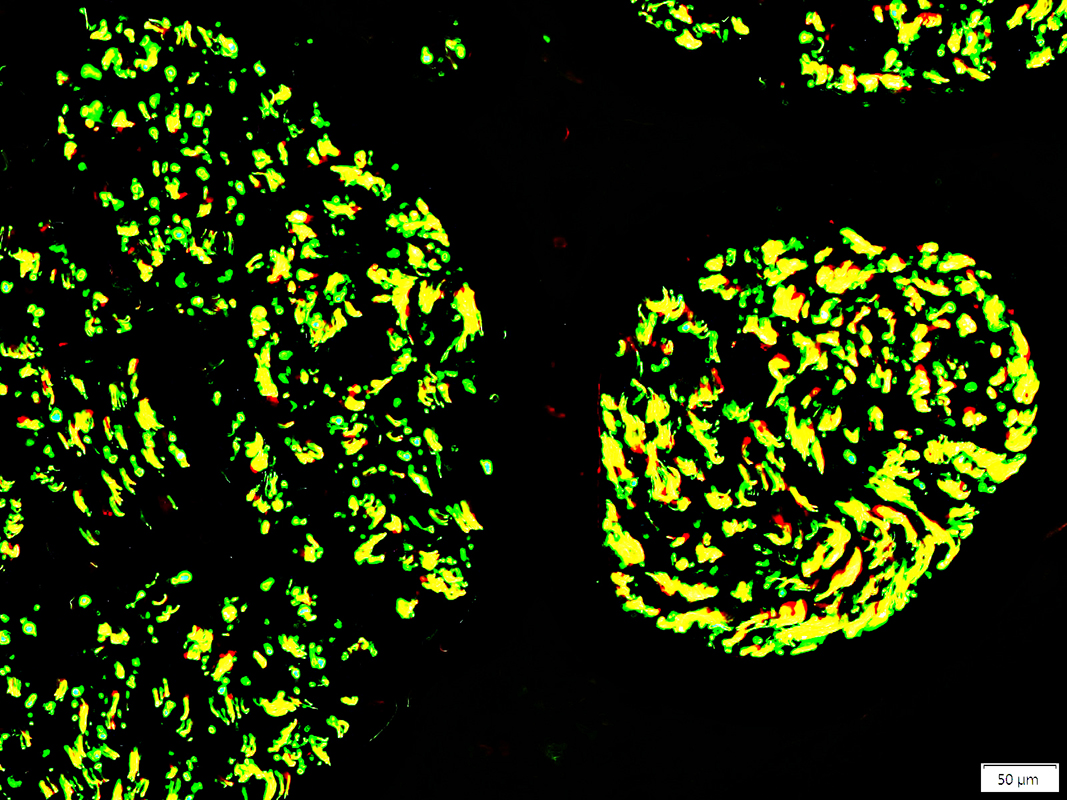

Neurofilament (Green), Myelin basic protein (Red) stain

Neurofilament stained axons in sural nerve (Yellow)

Lost within many MBP stained myelin sheaths (Red)

Unmyelinated Axons: preserved numbers (Green)

Neurofilament stained axons in anterior interosseus nerve (Yellow)

Lost within some MBP stained myelin sheaths (Red)